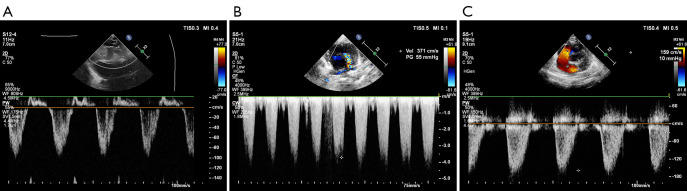

Methods: A retrospective analytical investigation was undertaken of 33 cases of neonates who underwent consecutive one-stage surgical repair for TOF at the Beijing Anzhen Hospital from June 2022 to December 2023. The subjects had an average gestational age of 38.1 weeks (range, 31.3-40.0 weeks) and a median age at surgery of 14.0 days [interquartile range (IQR): 9.75-20.0 days]. Their mean weight at the time of surgery was 3.25±0.53 kg, and their mean pulse blood oxygen saturation (SpO2) level was 93.0% (range, 80-98%).

Results: The mean duration for which aortic cross-clamping was performed during the surgical procedure was 74.24 minutes, with a standard deviation of ±16.33 minutes. The average duration of cardiopulmonary bypass (CPB) was 118.85±17.94 minutes. The average duration of postoperative mechanical ventilation was 110.6 hours (±89.2 hours). The patients' average postoperative intensive care unit (ICU) stay was 10 days (range, 6.75-13.25 days), and their median postoperative stay was 14 days (IQR, 11.75-15.5 days). Postoperative complications were observed in two patients (6%), who required peritoneal dialysis catheter insertion at the bedside to manage fluid imbalances. No further interventions nor mortalities occurred during the follow-up period. The median follow-up period after surgery was 201 days (range, 51-417 days).

Conclusions: The curative effect of TOF repair in the neonatal period is well-documented, with its ability to prevent the effects of pulmonary artery development and collateral circulation formation. Consequently, we suggest considering TOF repair during the neonatal period.